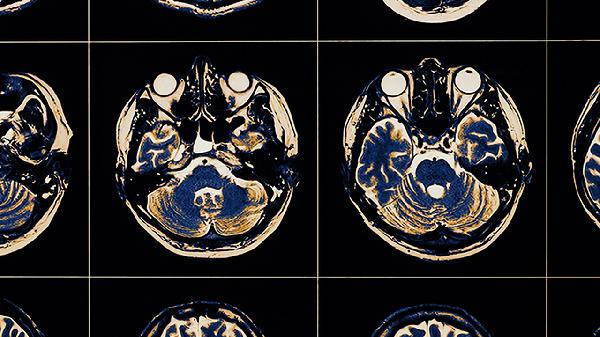

大脑不开窍可能由睡眠不足、心理压力过大、营养不良、脑部供血不足、神经系统疾病等原因引起,可通过调整作息、心理疏导、补充营养、改善血液循环、药物治疗等方式干预。

阿尔茨海默病早期、轻度认知障碍等疾病会损伤大脑认知功能,表现为进行性思维迟钝。这类情况通常伴随记忆力减退和定向障碍,可能与脑内β淀粉样蛋白沉积有关。需通过神经心理学评估确诊,早期可使用多奈哌齐等改善认知功能的药物干预。